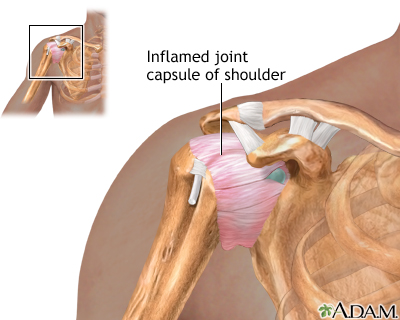

Viral arthritis is swelling and irritation (inflammation) of a joint caused by a viral infection.

The main symptoms are joint pain and swelling of one or more joints.

A physical examination shows joint inflammation. A blood test for viruses may be performed. In some cases, a small amount of fluid may be removed from the affected joint to determine the cause of the inflammation.

If joint inflammation is severe, aspiration of fluid from the affected joint may relieve pain.